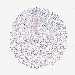

KIDNEY RENAL CLEAR CELL CARCINOMA (TCGA) - Interactive survival scatter ploti

The Survival Scatter plot shows the clinical status (i.e. dead or alive) for all individuals in the patient cohort, based on the same data that underlies the corresponding Kaplan-Meier plots. Patients that are alive at last time for follow-up are shown in blue and patients who have died during the study are shown in red.

The x-axis shows the expression levels (FPKM) of the investigated gene in the tumor tissue at the time of diagnosis. The y-axis shows the follow-up time after diagnosis (years). Both axes are complimented with kernel density curves demonstrating the data density over the axes. The top density plot shows the expression levels (FPKM) distribution among dead (red) and alive patients (blue). The right density plot shows the data density of the survived years of dead patients with high and low expression levels respectively, stratified using the cutoff indicated by the vertical dashed line through the Survival Scatter plot. This cutoff is automatically defined based on the FPKM cutoff that minimizes the p-score. The cutoff can be changed by dragging the vertical line or by entering a cutoff value in the square labeled "Current cut-off".

Under the Survival Scatter plot the p-score landscape (black curve; left axis) is shown together with dead median separation (red curve; right axis). Dead median separation is the difference in median mRNA expression between patients who have died with high and low expression, respectively. It is calculated as follows: median FPKM expression of dead patients with high expression - median FPKM expression of dead patients with low expression. This is intended to aid the user in visually exploring custom cutoffs and the associated p-scores and dead median separation.

Individual patient data is displayed and can be filtered by clicking on one or more of the category buttons on the top of the page. Categories describing expression level and patient information include: high, low, alive, dead, female, male and tumor stages. The scale of the x-axis can be toggled between linear and log-scale by clicking on the "x log" button. Mouse-over function shows TCGA ID, patient information and mRNA expression (FPKM) for each patient.

& Survival analysisi

Kaplan-Meier plots summarize results from analysis of correlation between mRNA expression level and patient survival. Patients were divided based on level of expression into one of the two groups "low" (under cut off) or "high" (over cut off). X-axis shows time for survival (years) and y-axis shows the probability of survival, where 1.0 corresponds to 100 percent.

IDUA is potential prognostic, high expression is unfavorable in Kidney Renal Clear Cell Carcinoma (TCGA)

Best expression cut offi

: 7.47

Average pTPM 5.6

Number of samples 521